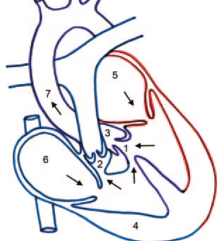

Tetralogie de Fallot

- Horizontalisation du Coeur (du à l’hypertrophie pulm)

- Signe du Coeur en Sabot (apex surelevé)

- Non visibilité du tronc pulmonaire

- Tetralogie:

- CIV

- Aorte à cheval

- Sténose et hypoplasie de l’infundibulum pulmonaire

- Hypertrophie du VD

- Si CIA associée = Pentalogie de fallot

- 1/4 des Fallots ont un arc aortique droit sans cardiomégalie ni vasculature pulmonaire augmentée (contrairement au TAC)